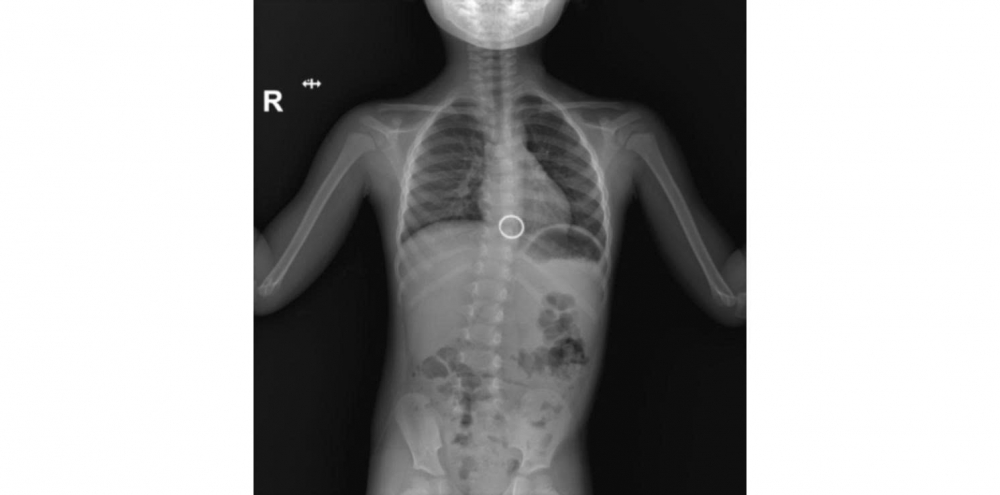

Theo đó, khoảng 13 giờ ngày 14/9, bé trai Trần Chí K (5 tuổi, ngụ xã Thạnh Mỹ Tây – An Giang) khi chơi đùa vô tình nhặt và nuốt móc chìa khóa bằng kim loại vào miệng. Ngay sau khi nuốt bé nói với cha, người nhà lo lắng đưa bé đi vào khoa cấp cứu bệnh viện. Qua hỏi bệnh và xem hình ảnh dị vật do người thân chụp bằng điện thoại các bác sĩ đã nhanh chóng hội chẩn, chụp X-quang, xác định vị trí dị vật trong đường tiêu hóa có nguy cơ tổn thương niêm mạc thực quản.

Đây là trường hợp dị vật đường tiêu hóa khó và nguy hiểm do bé còn nhỏ, dị vật to. Ngay lập tức ê kíp tiến hành hội chẩn phương án nội soi gắp dị vật có gây mê, chuẩn bị dụng cụ, .. và bắt đầu tiến hành nội soi gắp dị vật cho bé. Ống nội soi được đưa vào miệng đi xuống đoạn 1/3 dưới thực quản ghi nhận có hình ảnh móc khóa màu vàng dạng vòng nhẫn tròn. Ekip BS nội soi và gây mê tiến hành gắp móc khóa ra trong thời gian nhanh chóng khoảng 60 giây. Nội soi kiểm tra lại thấy dị vật chưa gây trầy sướt đường tiêu hóa. Bệnh nhi được theo dõi chờ hồi tỉnh sau gây mê và xuất viện sau 1 ngày nội soi can thiệp.